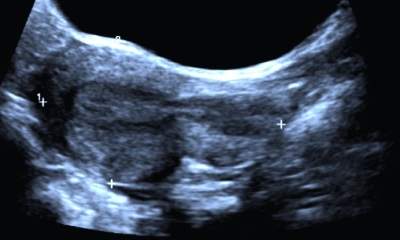

Thanks for your input, I would have been approx 11 weeks at the time of the scan image posted I did have another mid November. Still no talk just felt dismissed, no report just on my uterus measurements and Ovaries which was fine. I feel so challenged and then another person told me they could see a foot then another a femur. I feel like a pest but told to insist it be investigated further as bub might not be showing within the perimeters due to tilted uterus, no movement to date but would be approx 18 weeks and counting. My GP trips are getting to me mentally and I practically smile to myself knowing how predictable her text or narrative is going to be. This is Mid November someone told me they see a foot????? A femur as bones are usually bright but I fail to see this. Am I missing something. My health is otherwise great with pathology etc. Can't have TV as have had before and I leave spotting light pink for a day and half 2 days after the TV ultrasound therefore my GP agrees with me on one thing not to do TV anymore just abdo with full bladder. Kidneys, liver, spleen ovaries everything else is fine. I hope this child if there is one isn't squashed up or multiples distorting the pic. I would feel terrible but not at fault as no one is picking this up. I will attach the Nov scan for any feedback of feet or femur. Can you tell me the points they have marked out as no one explained again. TiA